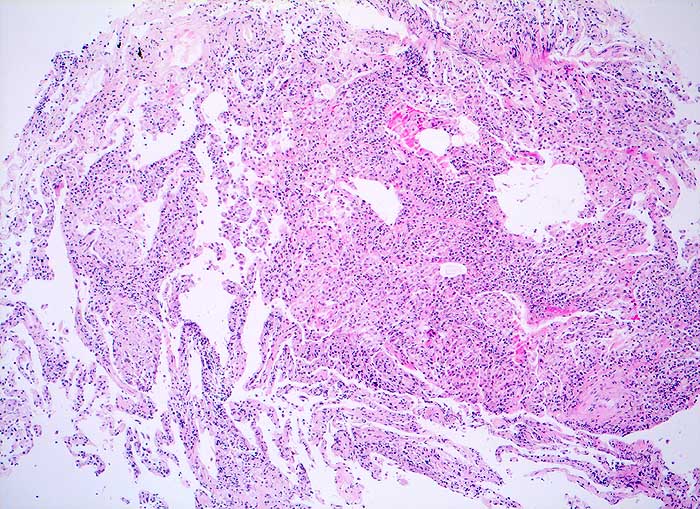

Die exogene allergische Alveolitis (Hypersensitivitätspneumonie) ist eine Entzündungsreaktion der Lunge, die bei prädisponierten Individuen durch pflanzliche oder tierische Inhalationsantigene ausgelöst werden kann. Die BAL Befunde hängen vom Stadium der Erkrankung ab. In der perakuten Phase überwiegen neutrophile Granulozyten. Ausserdem sind in den ersten Tagen der Exposition die Mastzellen auf über 1% erhöht (mehr als 3/10 HPF), um nach 1 bis 3 Monaten wieder auf Normalwerte abzufallen. Bei aktiver EAA besteht oft eine extreme Lymphozytose von 60-70%. Bei chronischer Erkrankung sind Schaumzellen, einige eosinophile Granulozyten und als Ausdruck der Fibrose reichlich neutrophile Granulozyten nachzuweisen. Eine Lymphozytose von mehr als 100x10^6/L in der BAL zusammmen mit einem erniedrigten HS Quotienten von unter 0.5 sind bei entsprechendem klinischen Verdacht vereinbar mit einer exogenen allergischen Alveolitis.